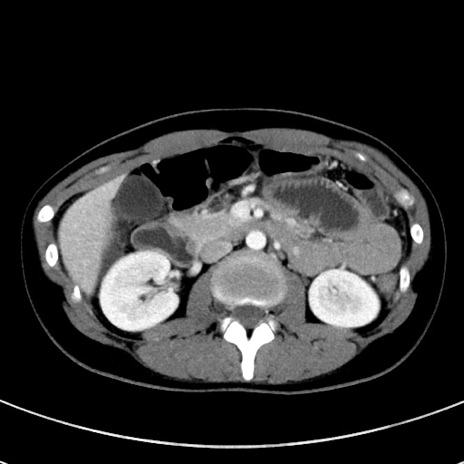

症例17(横断像)

【症例】20歳代女性

【主訴】嘔吐、下腹部痛

【現病歴】昨日夕食後に嘔吐し下腹部痛が出現。本日になっても嘔吐持続し改善しないため来院。

【身体所見】意識清明、BT 37.2℃、BP 108/67mmHg、腹部:平坦、やや硬、下腹部正中から右にかけて圧痛あり、反跳痛軽度あり、tapping pain(+)。

【データ】WBC 13600、CRP 14.94